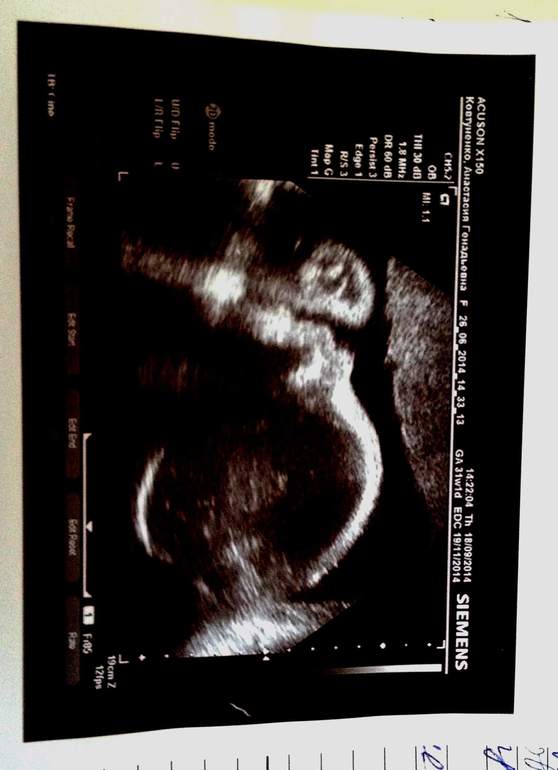

А ещё наконец-то могу похвастаться нашим Топтыгиным. Не отвернулся, помахал ручкой и зевнул. Хоть на узи (в полные 31) и сказали, что малыш опережает по весу на 1 недельку, мне так не кажется. Всего лишь 1736 г. Разве это много??? Почитала девочек и у некоторых по 200 кг уже. В общем посмотрим. Но я поняла, что подгузники которые нам достались в наследство нам уже малы:) Они подозрительного размера before newborn и по весу до 2 кг.

На прошлой неделе после узи мне поставили многоводие и неправильное положение детки. Но с деткой мы уже решили этот вопрос. Перевернула ег в течении нескльких дней! Укачала его. Значит, моряком ему не быть? А многоводие лечим. Со вторника капельницы. Самочувствие на отлично. Чего и всем желаю! Не болейте. Это сейчас так некстати.